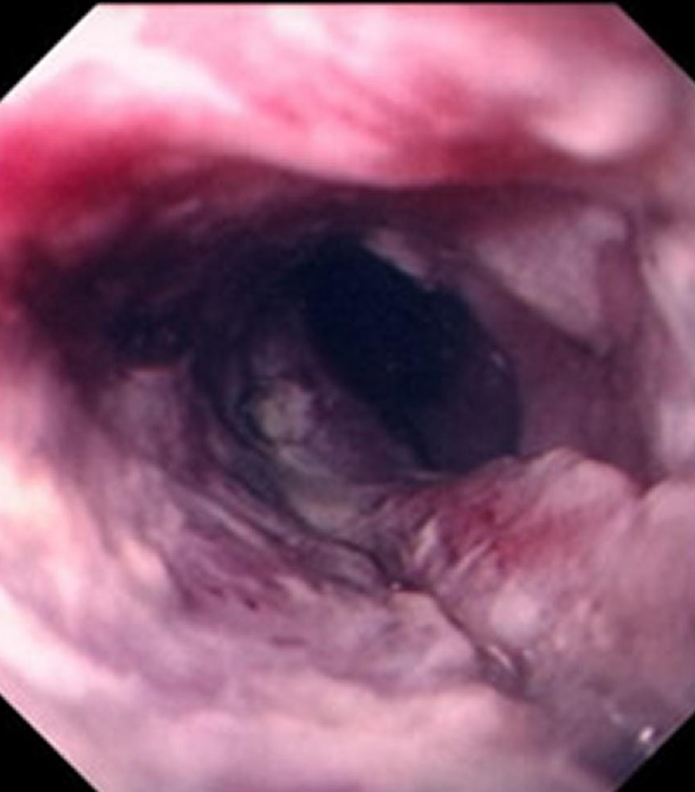

咽部黏膜充血增厚,其下部有广泛的结缔组织及淋巴组织增生,在黏液腺周围的淋巴组织增生,在咽后壁上形为多个颗粒状隆起,有时可融合成一片。慢性肥厚性咽炎可累及咽侧索淋巴组织,导致增生肥厚,而呈现条索状。

主要观察咽部黏膜是否有充血、水肿、分泌物附着等异常情况。此外,还可能会触摸颈部,以了解有无淋巴结肿大的情况。